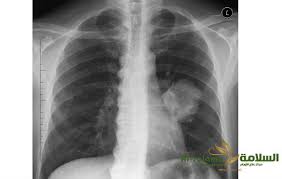

أعراض سرطان الرئة المتقدمة

اعراض سرطان الرئة المتقدمة